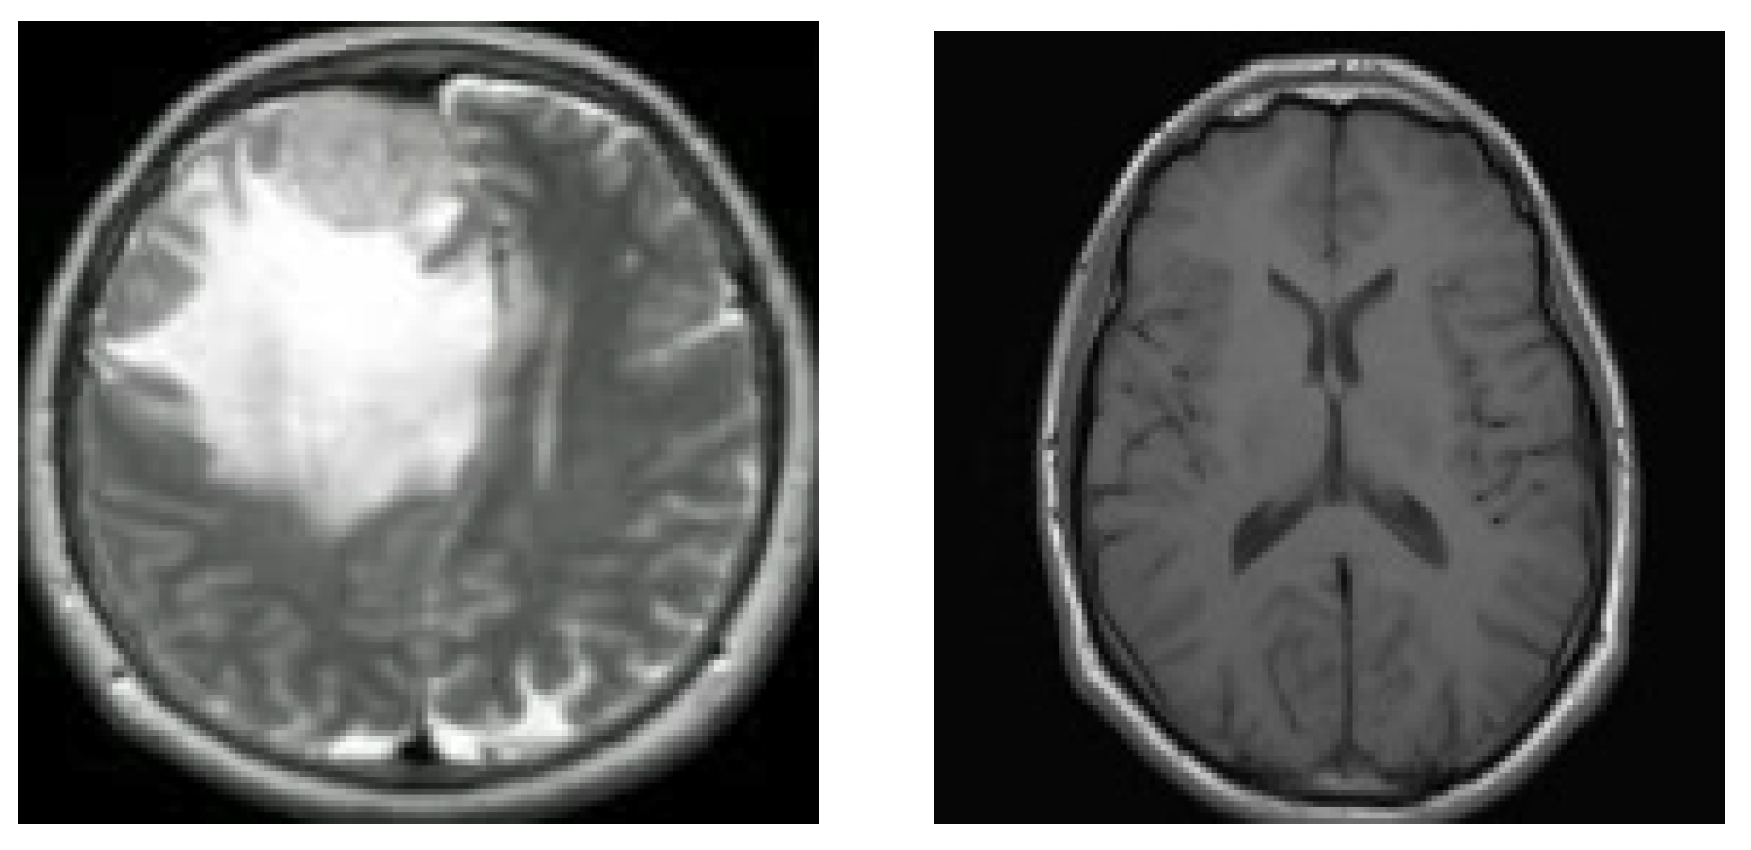

14]; it contains brain MRI images of glioma tumor, meningioma tumor, no tumor, and pituitary tumor, numbered 826, 822, 395, and 827, in that order. This collection of data is identified as dataset-Ⅲ in the current research. The four different kinds of brain MRI images that are present in dataset-Ⅲ are shown in

Figure 3.